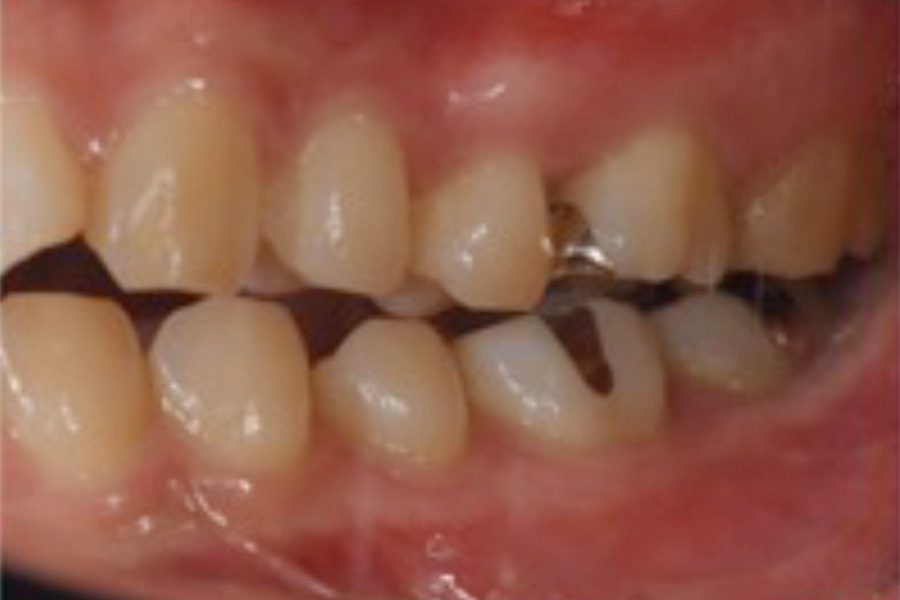

治療後

主訴 右上が気になる。下顎の歯並びを治したい。

治療内容 目立ちにくいマウスピース矯正(非抜歯矯正)

歯と歯の間に隙間をつくることにより、歯列弓を広げながら治療を行いました。